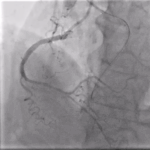

Η ορθόδρομη προσπέλαση αποτελεί την πλέον συχνά χρησιμοποιούμενη τεχνική στη διάνοιξη χρόνιας ολικής απόφραξης. Περιλαμβάνει την προσπέλαση της βλάβης από το εγγύς προς το περιφερικό άκρο της αρτηρίας, ακολουθώντας τη φυσιολογική φορά της αιματικής ροής.

Αν και είναι τεχνικά πιο απλή συγκριτικά με την οπισθόδρομη, ωστόσο η επιτυχία της περιορίζεται σε περιπτώσεις εκτεταμένης ασβέστωσης ή όταν η είσοδος της απόφραξης είναι ασαφής.

Από την άλλη, η ανάδρομη προσπέλαση εφαρμόζεται όταν η ορθόδρομη τεχνική αποτυγχάνει ή θεωρείται υψηλού κινδύνου. Αν και προσφέρει υψηλότερα ποσοστά επιτυχίας σε δύσκολες βλάβες, η ανάδρομη τεχνική απαιτεί μεγάλη εμπειρία και εγκυμονεί αυξημένο κίνδυνο επιπλοκών.